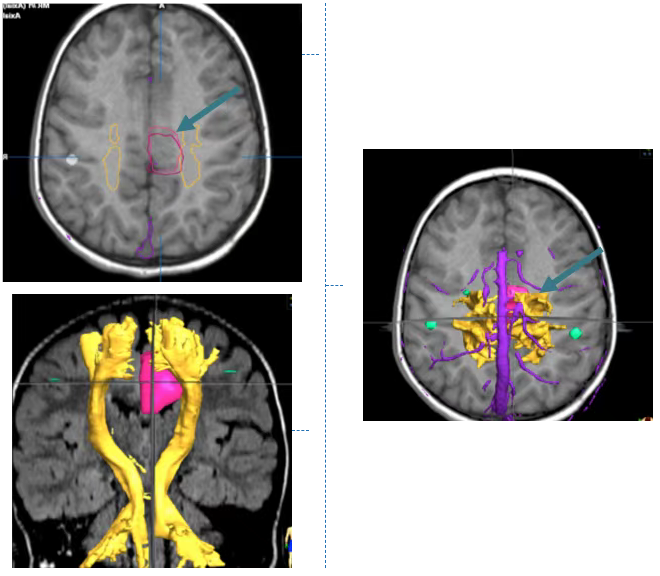

通过MRI,特别是弥散张量成像(DTI),可以清楚地看到小洛脑袋中的致痫灶。

鲁特卡教授借助术前详细的影像资料,为小洛制定了个体化的手术方案,并选择合适的手术入路。